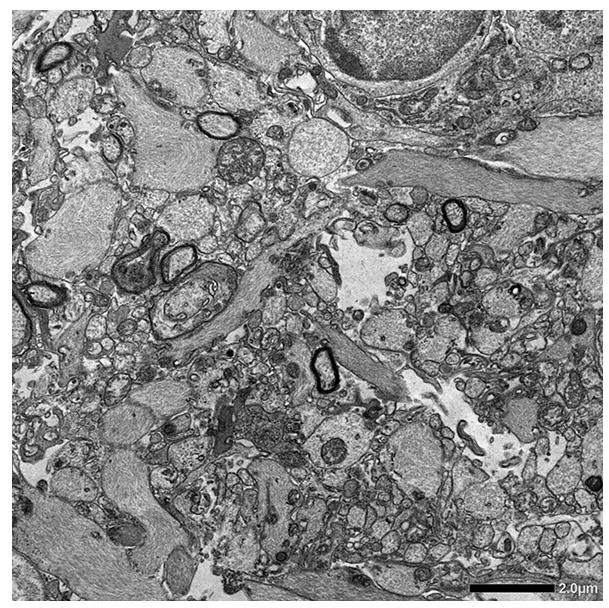

Low Magnification

Loss of coating around nerve cells with degeneration

(demyelination/loss of myelin & axons)